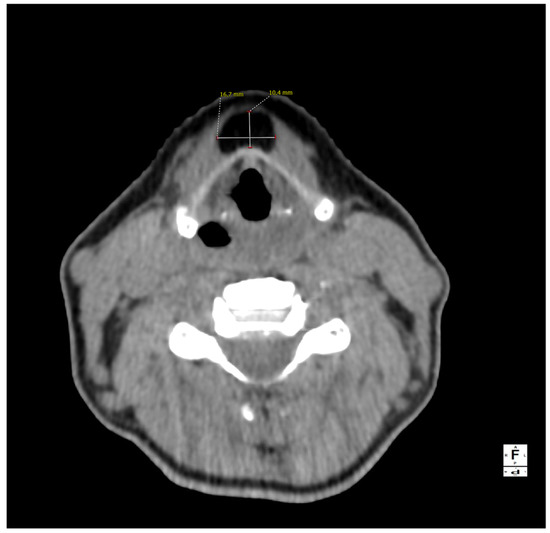

Figure 3.

Magnetic resonance imaging of the neck on a coronal plane, T2-weighted, showing the craniocaudal extension of the mass from the base of the tongue to the anterior neck region. Picture was highly suggestive of lipoma, therefore fine needle aspiration was not performed and the patient was referred for surgical excision under general anesthesia. A subperiosteal dissection was performed in the posterior surface of the hyoid bone that was not transected and the mass was isolated just below the hyoepiglottic ligament and without entering the pharynx. The patient was discharged without any pain or complication on the first postoperative day.